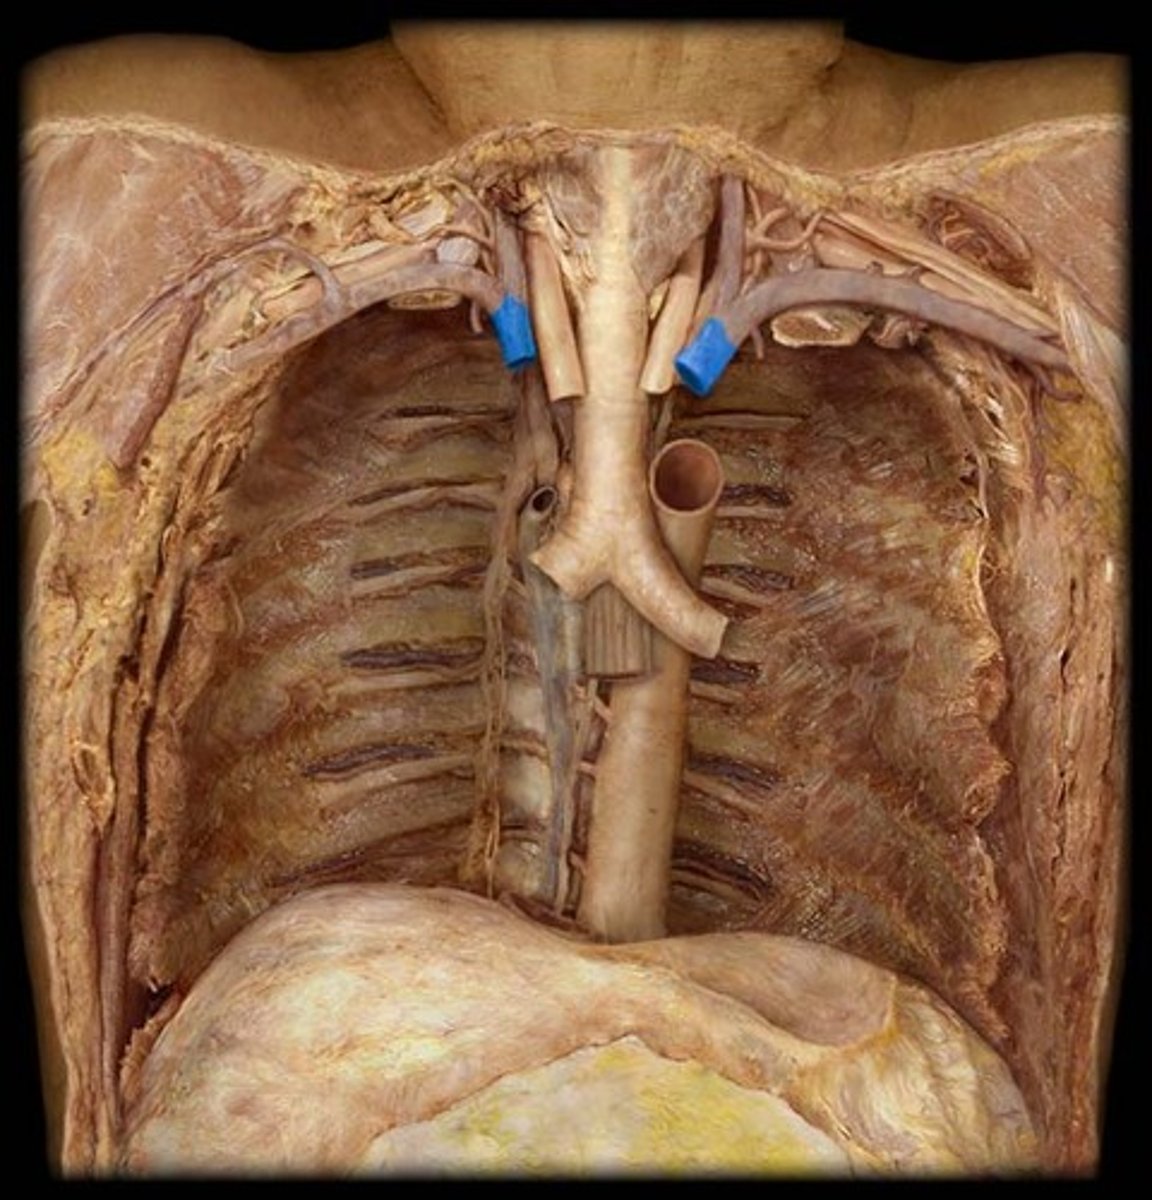

superior vena cava

Brachiocephalic veins